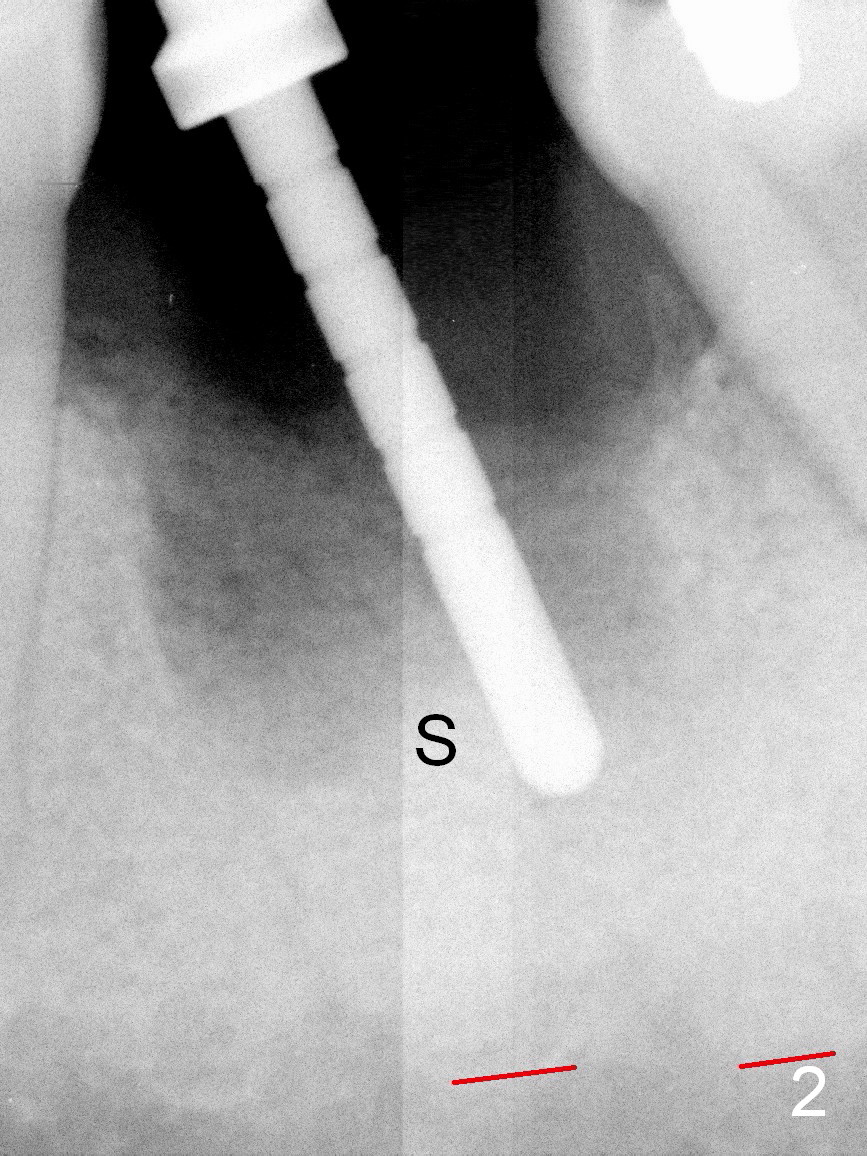

A 37-year-old lady (MP) presents to clinic with chief complaint of bad smell from lower right crown (Fig.1: #19; red dashed line: superior border of the Inferior Alveolar Canal). One of the most prominent pathologies is fracture of the distal root (<). After extraction, the socket is treated with 2% Xylocaine/1:50,000 Epinephrine. The coronal distobuccal plate is defective. Osteotomy is initiated as lingual as possible. The 1st intraop PA shows that the osteotomy is shallow and distal to the almost non-existent septum (Fig.2 S). The osteotomy is intended to move more mesially, but the result is not obvious when 4.5x14 mm drill is in place (Fig.3 D). The depth of the osteotomy is increased by 3 mm; a 5x17 mm tap is stable (Fig.4 T). A 5x12 mm implant (Fig.5 I) is placed until it cannot be turned. The implant is higher than the distal crest (^). In addition there is space apical to the implant (Fig.5*). After 5 mm drill is used, the implant is seated deeper with insertion torque < 35 Ncm (Fig.6). It suggests overprep. Anyway, an immediate provisional is fabricated after placement of an abutment (A). After reline, the provisional fits well. It has to be removed with forceps for occlusal adjustment. Finally the abutment/implant complex turns in the socket with fingers. The rotation/position of the complex is randomly adjusted. When the provisional is cemented, it does not seat completely, but is stable. If the implant osteointegrates, the provisional must play a role in stabilizing the implant. Bone graft is placed in the gap prior to cementation (Fig.6 *).